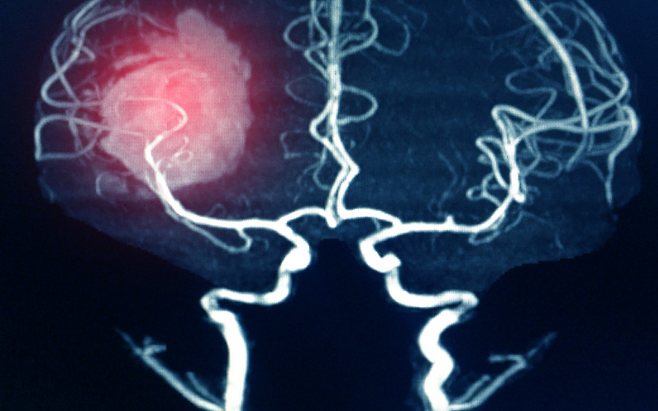

뇌출혈은 예고 없이 찾아오고, 한 번 겪으면 삶 전체를 송두리째 흔든다. 단 한 번의 출혈로 말이 어눌해지거나, 반신마비가 오기도 하고, 심할 경우 목숨까지 잃을 수 있다.

뇌출혈의 가장 큰 원인은 고혈압이다. 높은 혈압은 뇌혈관을 약하게 만들고, 결국 작은 충격에도 혈관이 터지게 한다. 혈압은 숫자가 아니라 생명줄이다. 하루 10분 걷기, 싱겁게 먹기, 충분한 수면, 스트레스 관리.